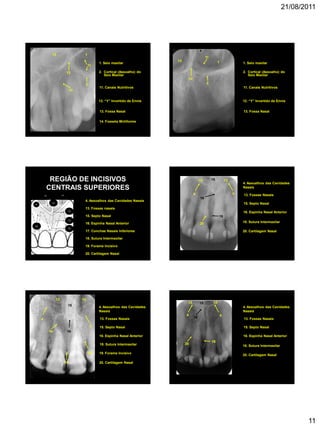

REGIÃO DE INCISIVOS

CENTRAIS SUPERIORES

4. Assoalhos das Cavidades Nasais

13. Fossas nasais

15. Septo Nasal

16. Espinha Nasal Anterior

17. Conchas Nasais Inferiores

18. Sutura Intermaxilar

19. Forame Incisivo

20. Cartilagem Nasal

15

4

16

19

18

13 17

20

13 13

4. Assoalhos das Cavidades

Nasais

4 4

20 19. Forame Incisivo

13. Fossas Nasais16

21/08/2011

12

16. Espinha Nasal Anterior18

17 17